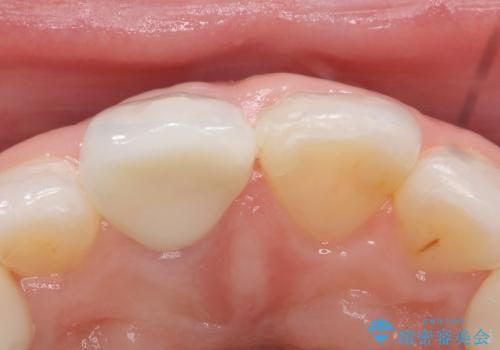

再根管治療終了後、オールセラミッククラウン(スペシャル)によって隣在歯に合わせた補綴を行いました。

前歯の補綴ではオールセラミッククラウンを希望される患者様が多いですが、オールセラミッククラウンの中でも、エコノミー、スタンダード、スペシャル、エクセレントとランクがあります。

その中でも特に審美性が高いのがスペシャル、エクセレントです。スペシャル、エクセレントは口腔内写真をもとに熟練の技工士が、患者様の口腔内に合わせたオーダーメイドのクラウンを製作致します。